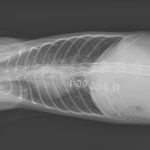

保護した猫さんの呼吸が早いかも??? かかりつけの先生に相談されたようです。エックス線検査で横隔膜ヘルニアが確定されました。外科的な対応を希望され来院されました。肝臓のほとんどが胸腔内にヘルニア(逸脱)しており、開腹アプローチで横隔膜を整復しました。正しい位置に臓器が戻ったので、これからは呼吸が楽になります。